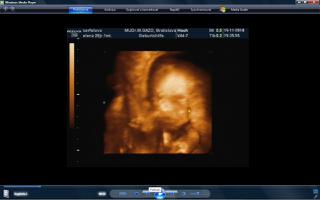

vcera som mala poradnu a teda dopadla pre mna dost prekvapujucu. mala je uz mesiac otocena dolu hlavickou a tlaci sa a tlaci. krcok sa mi zacal skracovat, ale zatial sa neotvara. a aby toho nebolo malo, tak mam aj iritabilnu maternicu. buducu nedelu idem do nemocnice na premeranie krcka a uvidi sa, co bude. aspon, ze ju uvidime 3D potvorku malu nedockavu 🙂 do mesiaca mi zrejme bude treba zaviest pesar.. tooolko radosti naraz a to som povodne vobec nemala mat poradnu, kedze som povodne dosla len s babkou na kontrolu..tak vysetrila aj mna.

caute baby. uz som tu dlho nebola. nejako nestiham. My sme uz boli na tiez na 3D a zase mala mala rucicky pred tvarickou ale daco bolo aj vidno. takze sme zistili, ze sa podoba na muza, teda aspon ten nos usta. Ma skoro 500 g takze je asi o tyzden posunuta neskor.Ak sa mi bude dat tak pridam dake fotky z toho dvd co som vybrala. Inac ja som kupovala tehotenske pancuchy v Brendone v Ba za 4 Eura. teda tenke ale mali tam aj hrubsie a tie stali 15 eur. Ja tiez rozmyslam rodit v ruzinove ale asi skor na Kramaroch. to mam blizsie domov. Ja si doplacam od marca dobrovolne nemocenske poistenie k povinnemu do maximalneho vymeriavaceho zakladu, aby som mala maximalnu matersku. Takze snad s tou materskou sa to bude dat ale horsie to bude s tym rodicovskym prispevkom.